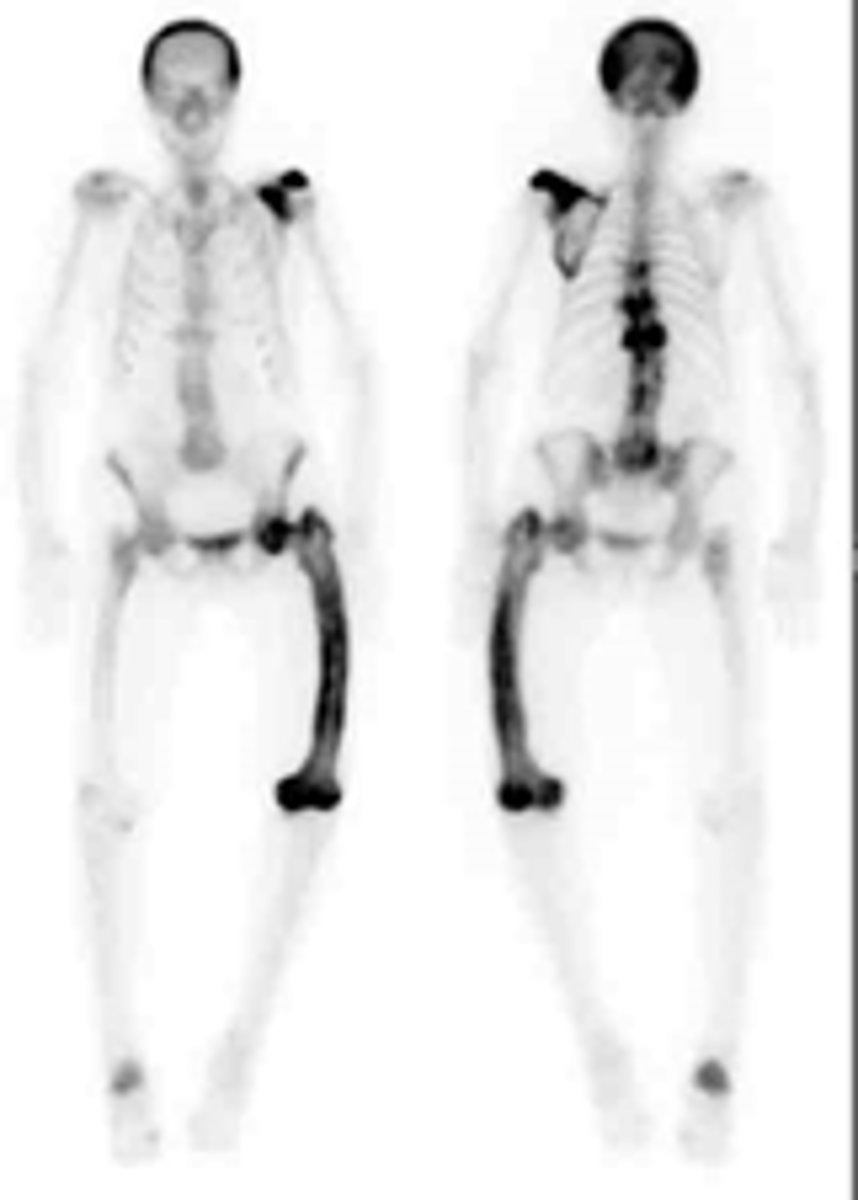

These are normal images of the legs with no significant pathologies being shown (the patient is 8 years old) (true/false)

True